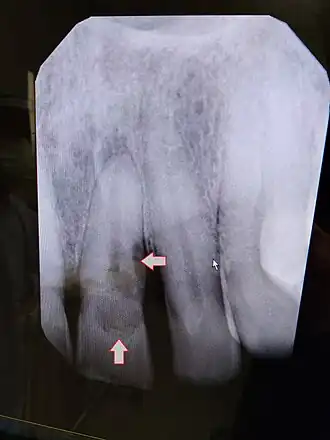

external root resorption premolar 25.

External resorption is the loss of tooth structure from the external surface of the tooth and is further subcategorized based on its etiology.[16]

x-ray of external root resorption premolar 25.

External replacement root resorption (ERRR) occurs due to replacement of the root surface with bone, i.e. ankylosis. ERRR can be further categorized as transient or progressive depending on the extent of periodontal ligament damage with the latter resulting in complete root resorption.[16]